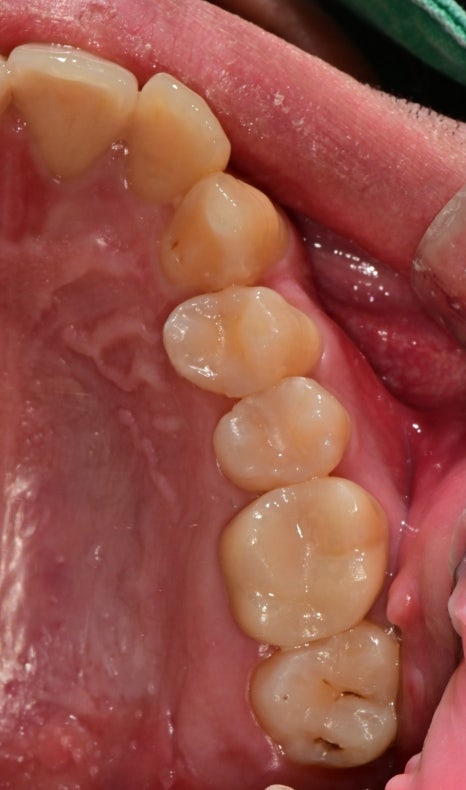

보철치료 후 교합조정

보철치료까지 완료된 사진입니다.

치료가 모두 종결된 후

초반에는 정기적으로 교합 체크를 진행했습니다.

후방부로 갈수록 치아 공간이 짧았고

교합이 긴밀하여 교합간섭을 없애고

다른 치아와 교합을 조화롭게 조정했습니다.

기존 치아의 파절이 생겼다는 것은

어느 특정 치아와 과교합이 일어난다는 뜻이기 때문에

정기적으로 교합은 계속 체크를 해줘야 장기간 동안 파절 없이 지내실 수 있을 것으로 기대됩니다.